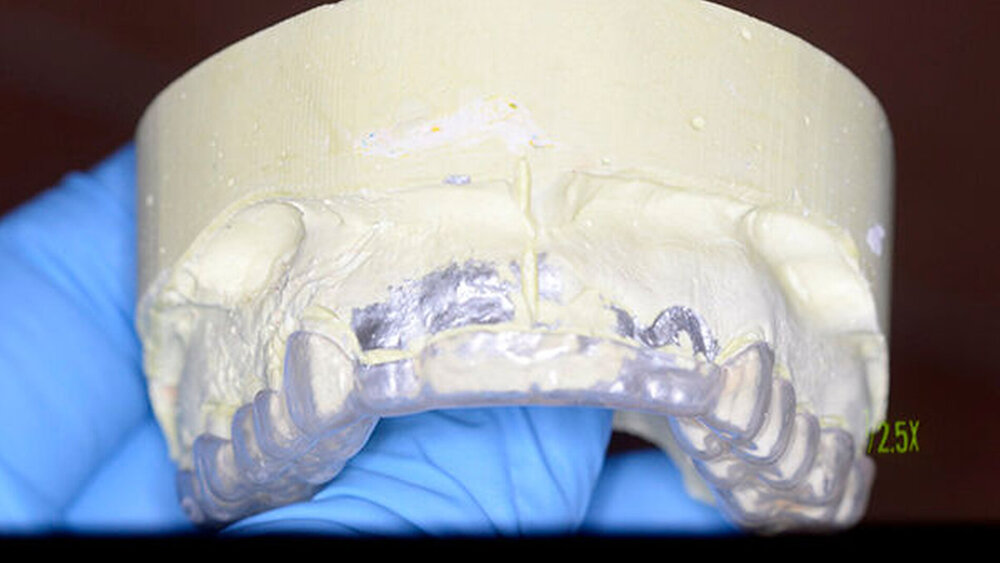

Der Zahn wurde zwei Stunden nach dem Unfall vital replantiert und semipermanent geschient. Die anschließende Abdrucknahme erfolgte unter allergrößter Sorgfalt. Die laborgefertigte Tiefziehschiene schließt die Bereiche der semipermanenten Schiene bis zum Schienenäquator mit ein. Was die Reanastomosierung der Gefäße und Nerven betrifft, ist der Behandler zuversichtlich, reagieren doch auch vital transplantierte Weisheitszähne nach einigen Wochen wieder auf Kältereize.